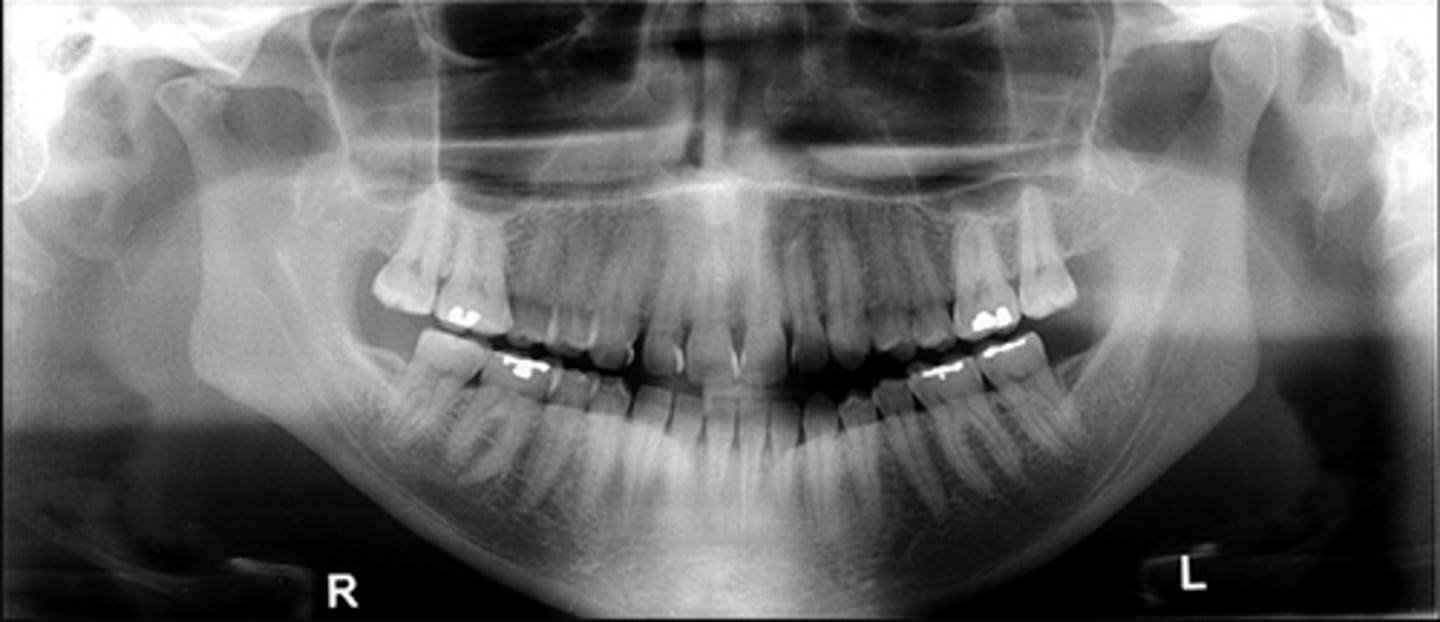

Patient has DJD.

The top images show the subchondral/ Ely cyst, a pseudocyst of connective tissue, granular tissue and osteoid, the bottom images show the same patients left side with broad erosion, a lack of cortication, loss of joint space.

What is the diagnosis of the patient based off these radiographs and what are the features? (Top images = patients right condyle) (bottom images= same patients left condyle)

Patient has DJD, there is significant erosion and loss of joint space.

A and B show prominent osteophyte formation at the anterior aspect

C shows multiple subchondral erosions

What is the diagnosis of the patient based off these radiographs and what are the features?